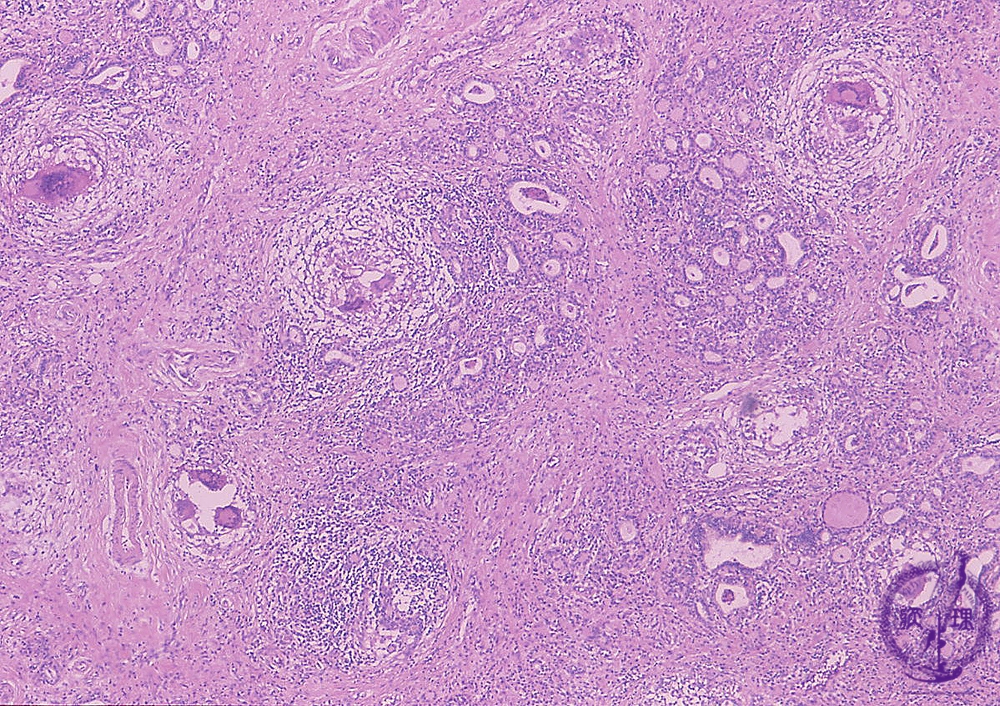

Microscopic findings (HE stain, low power view). Lymphocytic infiltration, atrophic thyroid follicles, fibrosis, and granulomas with multinucleated giant cells (dotted line), are observed in the thyroid.